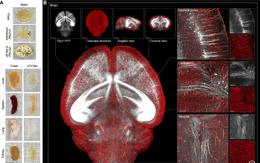

Công nghệ 'thủy tinh ion' mở kỷ nguyên mới cho nghiên cứu mô

Nhóm khoa học Đại học Thanh Hoa phát triển công nghệ làm trong suốt mô nội tạng, mở ra góc nhìn mới về cấu trúc cơ thể.